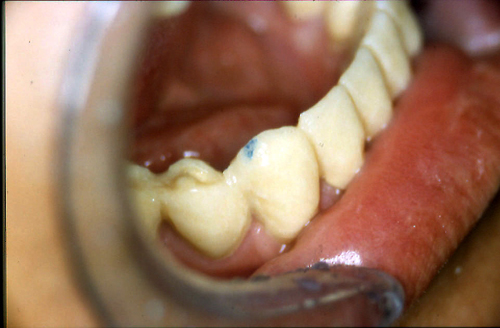

ABSTRACT El Bruxismo es una entidad patológica en la que concurren diferentes factores. Entre ellos el stress que conlleva consigo la vida moderna, constituye el Factor Predisponente sobre el que se ha abundado en innumerables tratamientos de tipo general, actuando sobre la psiquis y el comportamiento del individuo, ya sea con fármacos o bien mediante medios psicológicos. Sin embargo, como tantos desequilibrios provocados por el stress, confluyen siempre con un Factor Desencadenante, que en el caso del Bruxismo se encuentra en las desarmonías entre los componentes varios del Sistema Estomatognático. DESARROLLO Paciente varón, de 43 años, constitución atlética. A la inspección se observan desgastes oclusales que alcanzan la calidad de Facetas Parafuncionales, con dentina expuesta y empastes totalmente gastados y evidentes signos de falta de Disclusión Canina de ambos lados. Sobre dicho montaje se realiza un Encerado Progresivo de Diagnóstico, aportando en el mismo los elementos necesarios para obtener todos los principios básicos de una Oclusión Orgánica. FIG. 6 a 24 Una vez aprobado el fisiologismo de la oclusión en el articulador, se reproducen modelos de yeso con la nueva situación, y se estampa un SET UP en cada maxilar. FIG. 25/26 Procedemos entonces al tallado de las piezas correspondientes a la Guía Anterior, y rebasamos los estampados, creando en boca una nueva situación desoclusiva, que permanece en boca durante los pocos días que transcurren entre la primera y segunda visita de trabajo. FIG. 27/33 Ya abordando en esta segunda visita los sectores posteriores, tanto superiores como inferiores, tallamos siempre de manera supragingival, destacando la importancia vital de la forma obtenida en las provisionales, a las que abrimos plenamente las troneras para lograr una correcta higiene. FIG.34 a 43 FIG. 44 a 52 Efectuados los colados en oro y probados en boca, en el laboratorio se confecciona el bizcochado de la nueva Guía Anterior, la que puede o no copiarse de la Guía Anterior provisional, mediante la técnica denominada Trayectoria Funcionalmente Generada, que consiste en realizar en la platina del articulador un registro estereográfico sobre acrílico Duralay en polimerización. FIG. 57/58 Ajustados todos los detalles mediante esta técnica, se instala en boca en forma Provisional y se deja funcionando una semana o dos, al cabo de las cuales se chequean las disclusiones , los ajustes, la eficacia masticatoria, la carencia de sintomatología articular y muscular. FIG.59 a 63 PIE DE FOTO FIG.9 OBTENCIÓN DE LA GUÍA ANTERIOR FIG.10 Y 11 PITOMBOS. ALINEAC. TRIDIMENSIONAL FIG.12 PITOMBOS. DISCLUSIÓN DER. FIG.13 PITOMBOS. DISCLUSIÓN IZQ. FIG.14 WILSON INF. FIG.15 WILSON SUP. FIG.16 BOCA DE PEZ INF. FIG.17 BOCA DE PEZ SUP. FIG.18 VISTA OCLUSAL FIG.19 O.R.C. FIG.20 DISCLUSIÓN DERECHA FIG.21 CRESTAS TRIANG. INT. FIG.22 CRESTAS TRIANG. INT. FIG.23 CRESTAS TRIANG. INT. FIG 24 CRESTAS TRIANG. INT. FIG.59 DISCLUSIÓN IZQ. FIG.60 DISCLUSION IZQ. FIG.61 DISCLUSIÓN DER. FIG.62 DISCLUSION DER. FIG. 63 AJUSTE PERIFÉRICO